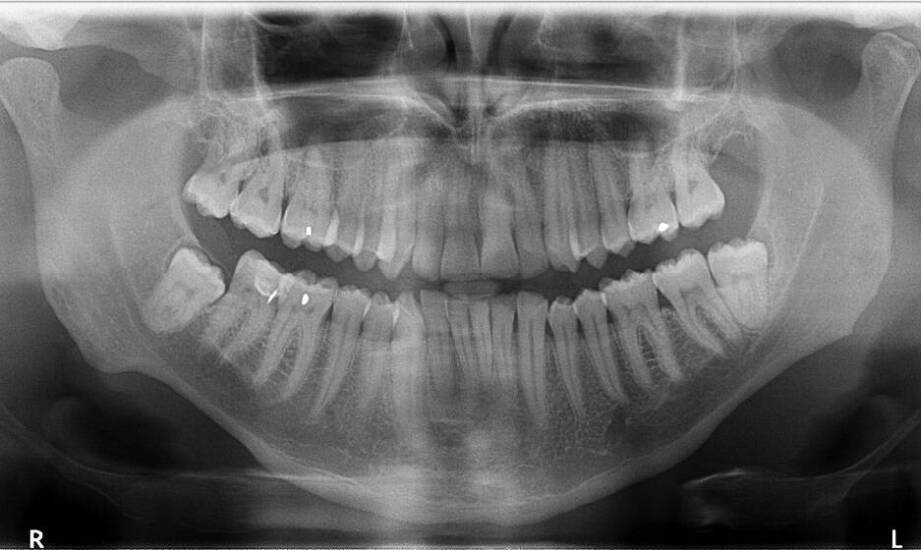

Tomografia komputerowa odgrywa kluczową rolę w diagnozowaniu problemów stomatologicznych, dostarczając szczegółowe informacje o strukturze zębów oraz tkanek otaczających. Dzięki tej technologii lekarze mogą identyfikować zmiany patologiczne, które mogą być niewidoczne w tradycyjnych zdjęciach RTG. W Skawinie specjaliści oferują tomografię komputerową zębów, co pozwala na dokładną analizę problemów jamy ustnej pacjentów. To wsparcie dla procesu diagnozowania chorób jamy ustnej, takich jak zębopochodne zapalenie zatok czy torbiele korzeniowe. Tomografia komputerowa jest również pomocna w planowaniu leczenia implantologicznego oraz ortodontycznego, umożliwiając ocenę warunków anatomicznych do przeprowadzenia zabiegów. Dzięki temu lekarze mogą opracować indywidualne plany terapeutyczne, które spełniają oczekiwania pacjentów i są dostosowane do ich potrzeb. Warto podkreślić znaczenie profesjonalizmu w branży stomatologicznej, zwłaszcza w kontekście stosowania nowoczesnych metod diagnostycznych, takich jak tomografia komputerowa zęba oraz inne innowacyjne rozwiązania dostępne w naszej okolicy.

Planowanie leczenia na podstawie obrazów 3D jest kluczowe dla osiągnięcia efektywności i bezpieczeństwa procedur stomatologicznych. Tomografia komputerowa zęba w Skawinie dostarcza trójwymiarowe obrazy, które pozwalają lekarzom dokładnie ocenić stan uzębienia oraz struktury anatomiczne pacjenta. Dzięki temu specjaliści mogą precyzyjnie zaplanować zabiegi, takie jak implantacja czy leczenie kanałowe. W przypadku implantacji stomatologicznej tomografia umożliwia ocenę ilości i jakości kości, co jest niezbędne do wyboru odpowiedniego implantu oraz określenia jego lokalizacji. Taki proces pozwala uniknąć powikłań i zwiększa szanse na sukces zabiegu. W kontekście leczenia kanałowego obrazowanie 3D pomaga zidentyfikować dodatkowe kanały korzeniowe oraz ocenić stopień ich skomplikowania, co przekłada się na lepsze wyniki terapeutyczne i mniejsze ryzyko nawrotów problemów stomatologicznych.